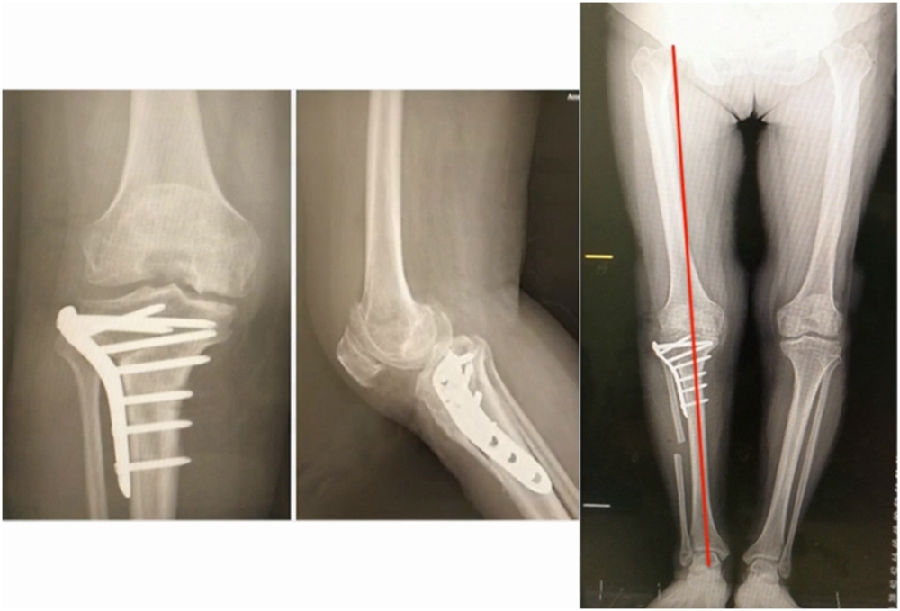

术后X线

典型病例,男性,65岁,农民,双膝内翻16度。

术前影像

第一次为该患者做了传统上行开放截骨,撑开角度较大,术后用三种方法测量髌骨高度,发现髌骨高度受到影响,髌骨变低了。

左膝上行OWHTO(初次)

上行OWHTO髌骨高度测量

ISI法测量髌骨无明显变化;CDI、BPI法测量髌骨降低明显;患者屈膝锻炼困难。

第二次来院做另一侧肢体时,采用下行截骨,术后患者髌骨高度,无论用哪种方法测量都无明显变化,而且患者膝关节功能迅速得到恢复。

右膝下行OWHTO(再次)

下行OWHTO髌骨高度测量

ISI法测量髌骨无明显变化;CDI、BPI法测量髌骨无明显变化;患者屈膝明显改善。